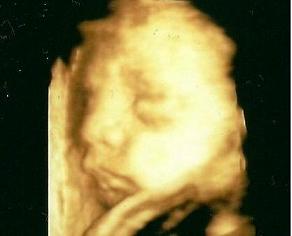

Na, és akkor jöjjön a durci Bendegúz :-D folyton az arca elé kapkodta a kezeit, és dacosan összeszorította a száját, nem tetszett neki :-)

Kép Kép

Amúgy minden rendben vele, műxik rendesen, 1054 grammosnak saccolta a gép :lol: